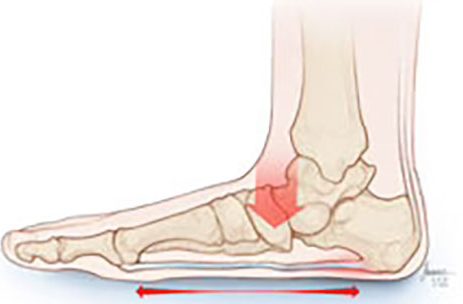

Subtalar Arthritis

Subtalar Arthritis is generally categorized as pain in the hindfoot. The subtalar joint is the joint that lets you rotate your foot back and forth and bend it back and forth. Patients who suffer from Subtalar Arthritis will feel pain when walking or moving the ankle. WHAT CAUSES SUBTALAR ARTHRITIS? Subtalar Arthritis is usually caused by a fracture in the foot, usually the heel bone. It can also be caused by excessive wear and tear on the joints resulting from too much activity. HOW DO I KNOW IF I HAVE SUBTALAR ARTHRITIS? WHAT ARE THE SYMPTOMS OF SUBTALAR ARTHRITIS? The most common symptom of Subtalar...

Flat Foot/Fallen Arch

Flatfoot, or more commonly known as Flat Feet, is the most common condition associated with bottom arch pain. Pronation is the natural movement of your foot while walking. The movement includes your ankle, heel, and arch and distributes the weight evenly throughout your foot. Your ankle naturally rolls inward momentarily to account for the shift of weight during movement. Overpronation is what happens when the ankle rolls too far inward on a regular basis and forces the inside of your foot to handle the weight. Over time this causes your arch to flatten, your tendons to loosen, your joints to become instable,...